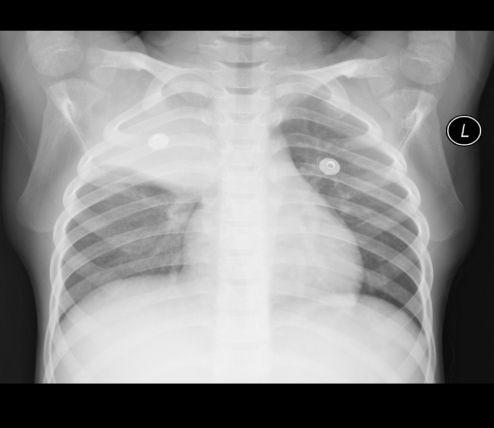

当然,外观再炫酷,如果没有强大的功能,那也是徒有其表。2025年的胸片在功能上可谓是全面升级。首先,它具备智能监测功能,可以实时监测你的心率、血压、呼吸等生命体征,让你对自己的健康状况了如指掌。此外,它还具备智能提醒功能,当你长时间保持同一姿势时,它会自动提醒你调整,预防颈椎病等职业病。